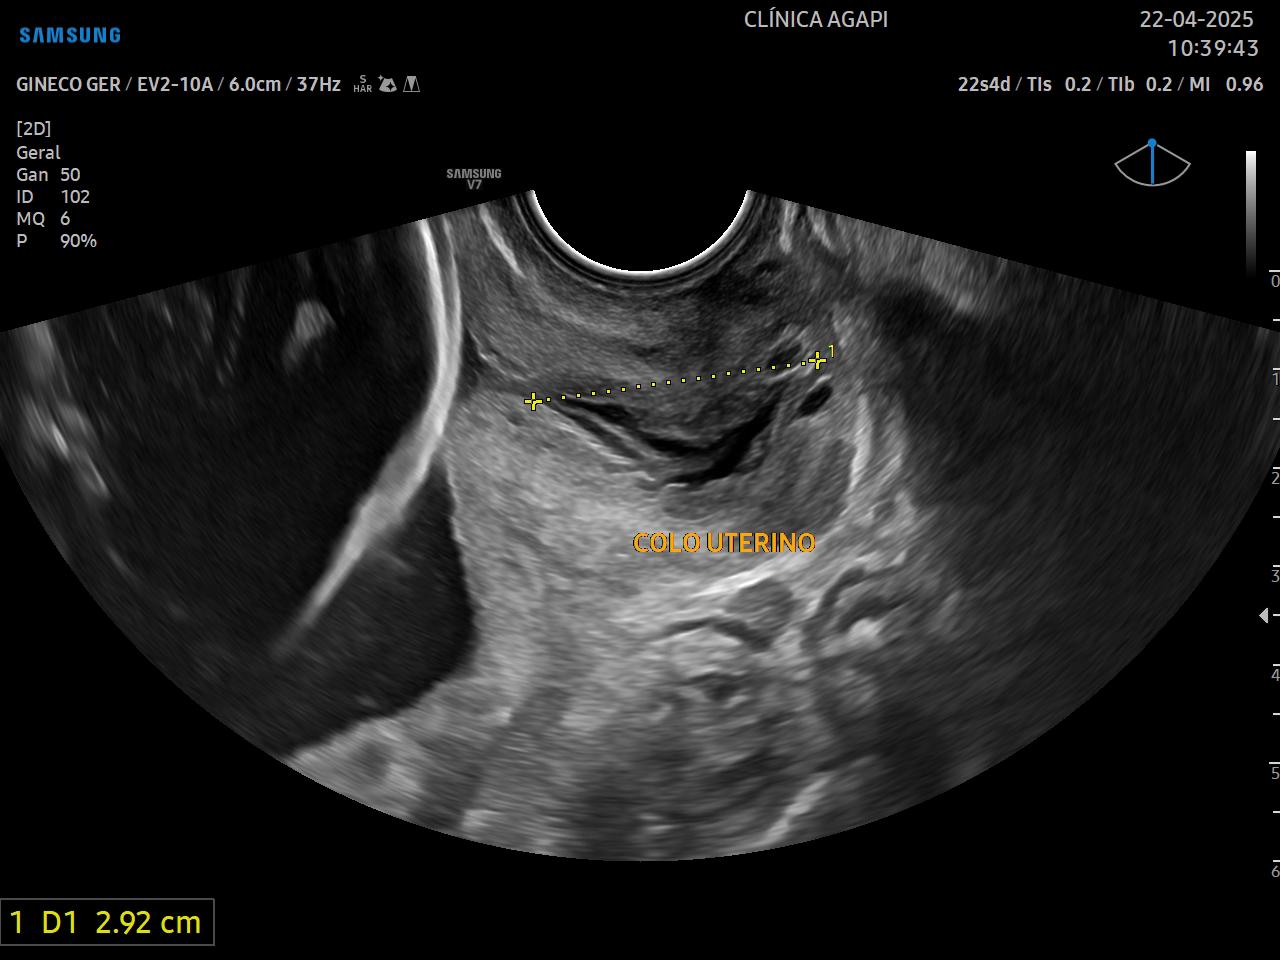

Tem por objetivo identificar pacientes com colo curto, sendo este um dos principais fatores de risco para parto prematuro. O melhor momento para se realizar essa medida é no segundo trimestre.

Através dessa avaliação, pacientes com alto risco podem ser tratadas com medidas preventivas e terapêuticas que visam diminuir o risco do parto prematuro.

Dada a importância deste exame na prática obstétrica, na Agapi, incluímos a medida do colo uterino em TODAS as pacientes que realizam o morfológico de primeiro e/ou segundo trimestre.